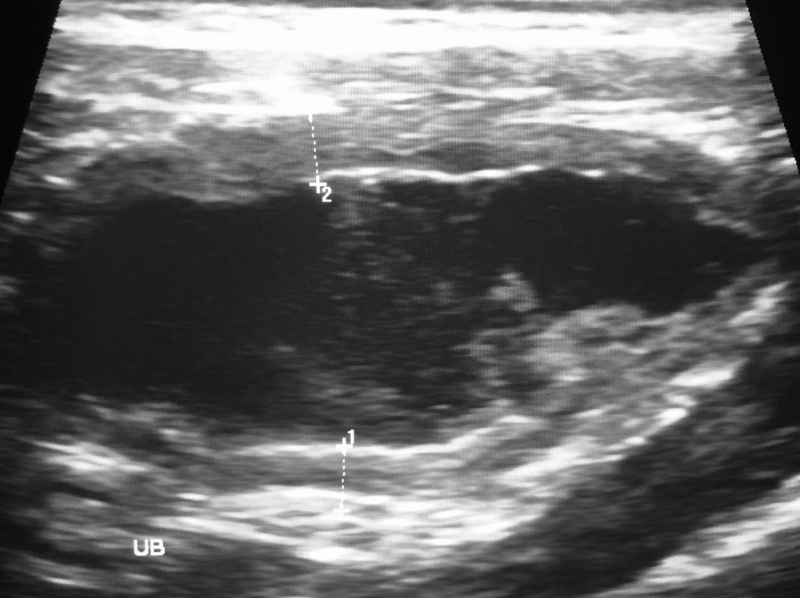

超音波検査

獣医が警察に電話したとき、直ちに向かうと言われた。このライオンは、単なる獣医の手術以上に特別な助けを必要としていたのだ。このライオンの胃の中では、明らかに何らかの奇妙なことが起こっていたため、手術ももちろん必要だった。まさに生と死にかかわる事態だったのだ…。

検査の結果

Source: Shutterstock.com/Maxim Gutsal

超音波検査の結果を見たとき、獣医はすぐに警察に通報した。この結果から、ある奇妙な行動を疑ったからだ。このとき、どうやら警察は手術の応援のためにすでにその地域にいたようだ。そして、警察はまず、最初の尋問にジョージを呼んだ。一体なぜジョージを?!

胃に何かある